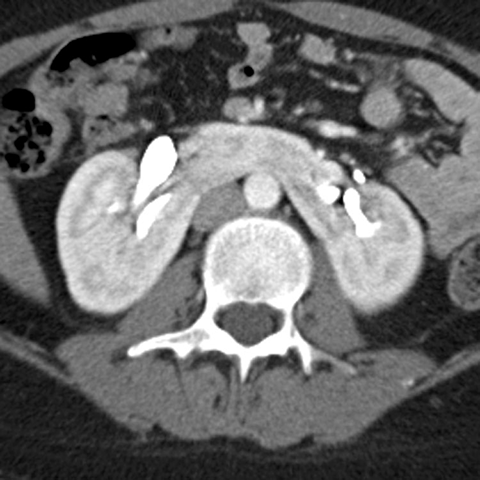

12-year-old-male presents with occasional abdominal discomfort [2 of 4]